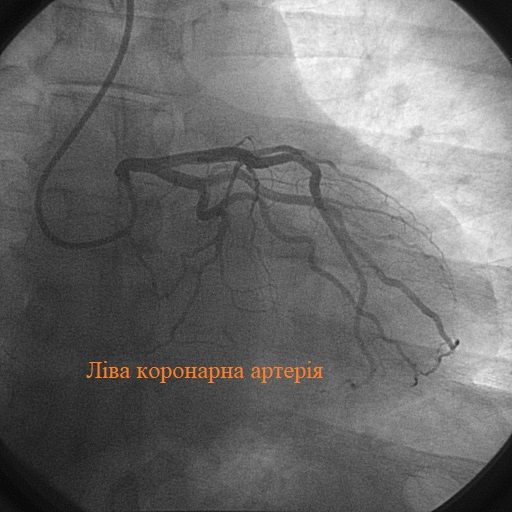

- Введення контрасту: На цьому етапі ви майже супергерой, ваше серце світиться на екрані.